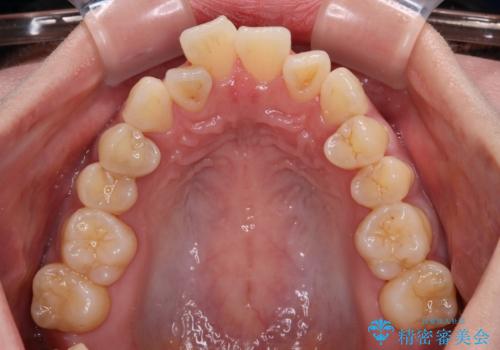

- 上下前歯のデコボコやクロスバイトを気にして来院された患者様です。

上顎歯列が下顎の歯列に対して狭小であり、一部下顎の奥歯が上顎よりも外側に位置している状態でした。

上顎の急速拡大装置を使用して上顎骨を側方に拡大することで上顎歯列を拡大し、下顎歯列も拡大できるようにすることで、歯列を整えることとしました。